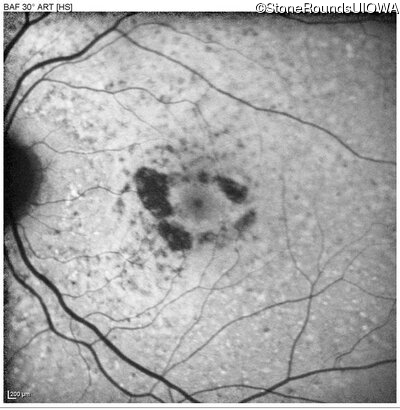

Pattern Dystrophy (IIC)

Age at visit: 62 years

This 62 year old man first noted mild distortion in his vision in his 30's, but has always been correctable to 20/20. One year ago an optometrist told him there were pigment abnormalities in his macula.

Diagnosis & molecular findings

Disease Gene Allele 1 variant(s) Allele 2 variant(s) Inheritance mode

Pattern Dystrophy PRPH2 Lys153Glu AAG>GAG   AD